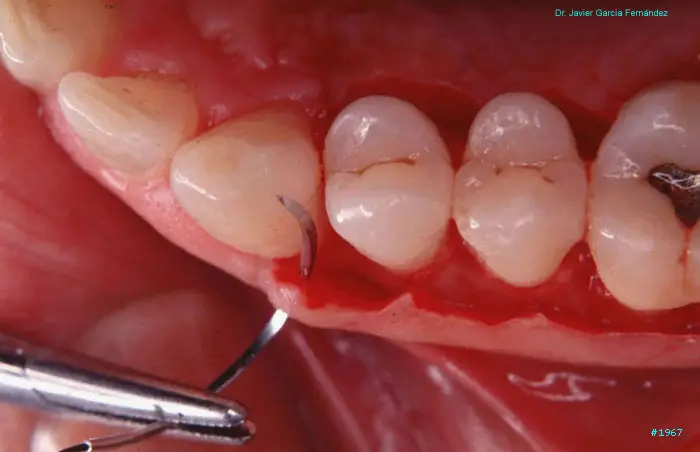

Atlas of Surgical Techniques in Periodontics. Chapter II. Atlas de Técnicas Quirúrgicas en Periodoncia